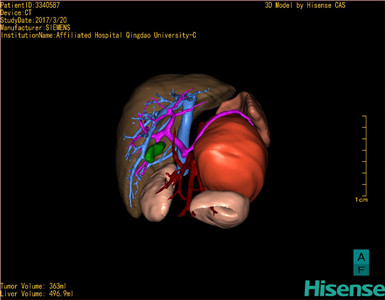

将0.625mm双源薄层CT资料的静脉期和动脉期Dicom格式文件导入海信CAS系统。

通过调节窗宽窗位调整CT序号,对肿瘤,肝实质,胆囊,下腔静脉,肿瘤,肝动脉、门静脉及肝静脉等进行三维重建;系统自动计算肿瘤体积和肝脏体积。

模拟手术操作,自动计算切除肿瘤体积。肝脏体积为496.9ml,肾上腺肿瘤体积363ml,术前规划手术方案,进行手术。

术前三维重建:

重建图片